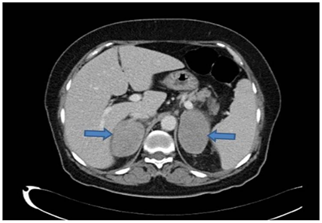

58-year-old woman referred to our endocrine clinic with bilateral adrenal mass found incidentally on computed tomography (CT) of the abdomen during a workup for abdominal pain. She has a history of abdominal pain associated with decreased appetite, marked weight loss and fever with night sweating for 1 year which had been progressive over the last few months,. No history of paroxysmal attacks of palpitation or headache, nor history of hirsutism. Past medical history was rlevant for type 2 diabetes mellitus; hypertension and she had hypoglycemic attacks, postural dizziness. She was off her antihypertensive medications and oral hypoglycemic medications for 1-month prior to presentation. On clinical examination, she was pale. Blood pressue 124/60, and pulse 85/minute and regular. No skin pigmentation, no lymph node enlargement. Her abdomen was soft, with no tenderness or organomegaly. Laboratory investigations showed a hemoglobin of 8.1 g/dL, Hemoglobin; A1c 4.9, sodium and potassium were normal, Erythrocyte sedimentation rate; 120 mm/hr (< 20 mm/hr), Lactic acid dehydrogenase; 1400 IU/L (250 and 500 IU/l). CT abdomen showed large, well defined with homogeneous enhancement bilateral adrenal masses 7.5 x4.9 cm and nor hemorrhage or calcification were seen with large para-aortic lymph node 4.4 cm (Figure 1). The adrenal masse work up showed: Aldosterone 3.7 ng/dL (3.5–37.1), Renin 4.2 ng/ml/L (0.76–4.61), Plasma free metanephrine ≤0.03 nmol/L (0.03–0.85), Pasma free normetanephrine 0.44 nmol/L (0.04–1.39), Dehydroepiandrosulf (DHEA-S ≤ 0.8mmol/L (0.8–4.9). Patient clinical condition deteriorated and admitted with severe abdominal pain, vomiting and hypotension refractory to the intravenous fluid. Adrenal insufficiency was highly suspected. Random serum cortisol was extracted and hydrocortisone I.V was started. Random serum cortisol level was 59 nmol/L (171-536). No Adrenocorticotropic hormone (ACTH) level was obtained. Short synacthen test was not done because of rapid deterioration of her clinical condition. Chest X-ray showed bilateral pleural effusion, aspiration cytology of the pleural fluid showed atypical large lymphocytes, suspicious of malignant lymphoma. Fine needle aspiration from Left para-aortic mass was consistent with diffuse large B-cell lymphoma (Figure 2A) (Figure 2B). Patient condition deteriorated further, and she passed away.

Figure 1 CT scan of abdomen (Portal venous phase axial) showed large, well defined with homogeneous enhancement bilateral large adrenal masses (blue arrows), nor hemorrhage or calcification were shown.